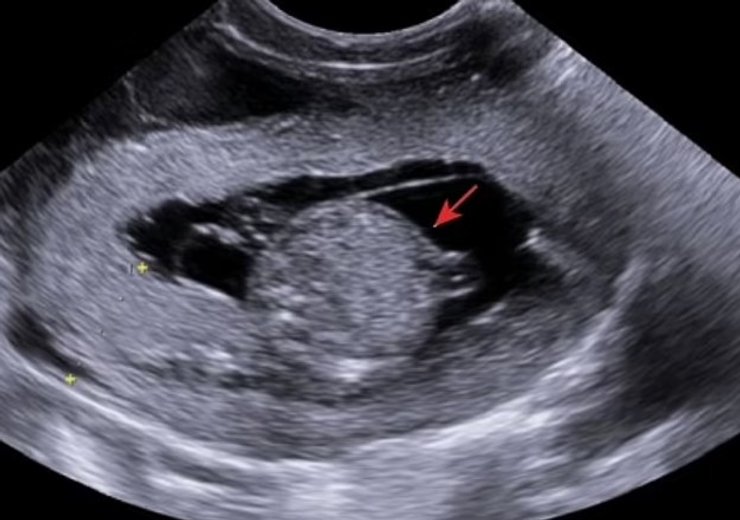

клонування ембріон

Ультразвукове дослідження плода-резуса на 60-й день вагітності

Фото: Nature Communications